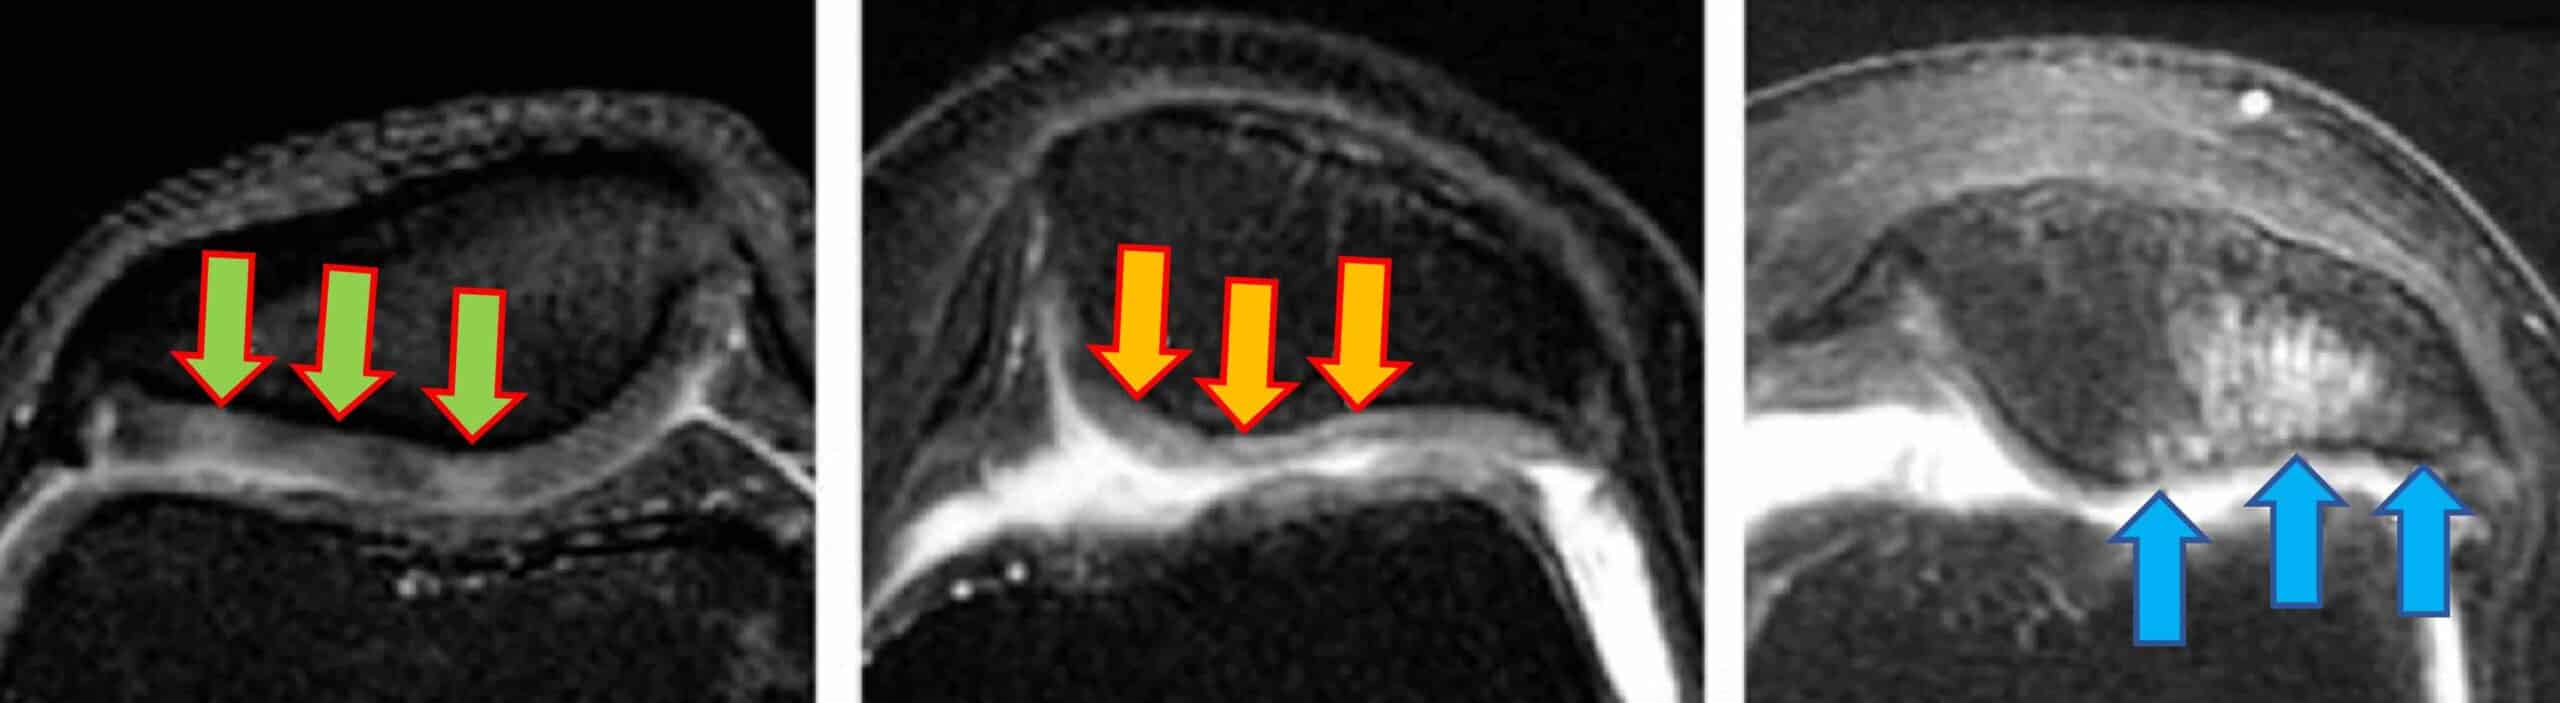

A condromalácia patelar é uma doença da articulação do joelho caracterizada pelo amolecimento e subsequente degeneração da cartilagem da patela, o osso móvel localizado na frente do joelho. Antigamente a patela era chamada de rótula. A face interna da patela tem uma espessa camada de cartilagem hialina que provê uma superfície lisa para que a patela deslize sobre a cartilagem da tróclea femoral, que é o sulco localizado na frente do fêmur distal onde a patela se articula. A cartilagem da patela é a cartilagem mais espessa do nosso corpo. Dor, rangidos e inchaço são os sintomas mais comuns da condromalácia patelar. A doença pode ser causada por inúmeros fatores predisponentes. Normalmente existem mais de um fator predisponente para o desenvolvimento da condromalácia na patela nos joelhos dos pacientes acometidos pela patologia, que é uma condropatia. Os onze fatores predisponentes mais conhecidos e estudados são: desalinhamento da patela, fraqueza muscular, desequilíbrio muscular, alterações anatômicas, lesões anteriores, sobrecarga mecânica, sedentarismo, obesidade, envelhecimento, fatores hormonais e fatores genéticos.

O desalinhamento patelar acontece quando a patela não se movimenta corretamente dentro da tróclea femoral, que é o sulco no fêmur onde a patela desliza quando se movimenta o joelho. O desalinhamento patelar sobrecarrega áreas específicas da cartilagem. Essa sobrecarga anormal localizada contribui para o amolecimento e desgaste da cartilagem patelar.